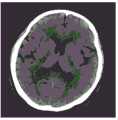

图17A-17F示出根据本公开的一些实施例基于迭代重建而生成的六个X射线图像;以及17A-17F illustrate six X-ray images generated based on iterative reconstruction according to some embodiments of the present disclosure; and

图18A-18B示出根据本公开的一些实施例基于迭代重建而生成的两个X射线图像。18A-18B illustrate two X-ray images generated based on iterative reconstruction according to some embodiments of the present disclosure.